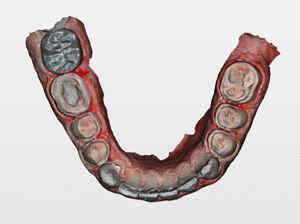

Mme AB vient en consultation pour deux raisons. La première est une douleur intense à chaque fois qu’elle boit ou mange froid. La deuxième est l’apparence de son sourire. Elle trouve que ses dents ont « raccourci » et qu’elles « s’effritent ». C’est devenu un complexe handicapant. À L’examen clinique on observe (Fig.1a, b, c, d, e) une usure vestibulaire de toutes les dents : plus prononcée au maxillaire et assez légère sur les incisives mandibulaires, une classe III canine et molaire droite, une classe I canine et molaire gauche avec une légère déviation des milieux et une usure importante des faces palatines du bloc IC maxillaire ainsi que des faces occlusales de 16 et 26. On constate aussi que les faces occlusales des autres dents sont moins touchées en apparence. On observe que les amalgames de 36 et 48 sont en relief par rapport à la dent support. Il est raisonnable de supposer qu’à l’origine ils devaient obturer une cavité et donc être à l’intérieur de la dent. Ceci témoigne donc aussi d’une forte usure sur 36 et 46. On observe enfin que les courbes de Spee sont complètement plates.

Fig.1a, b, c, d, e : Examen clinique.

Fig.1b.

Fig.1c.

Fig.1d.

Fig.1e.